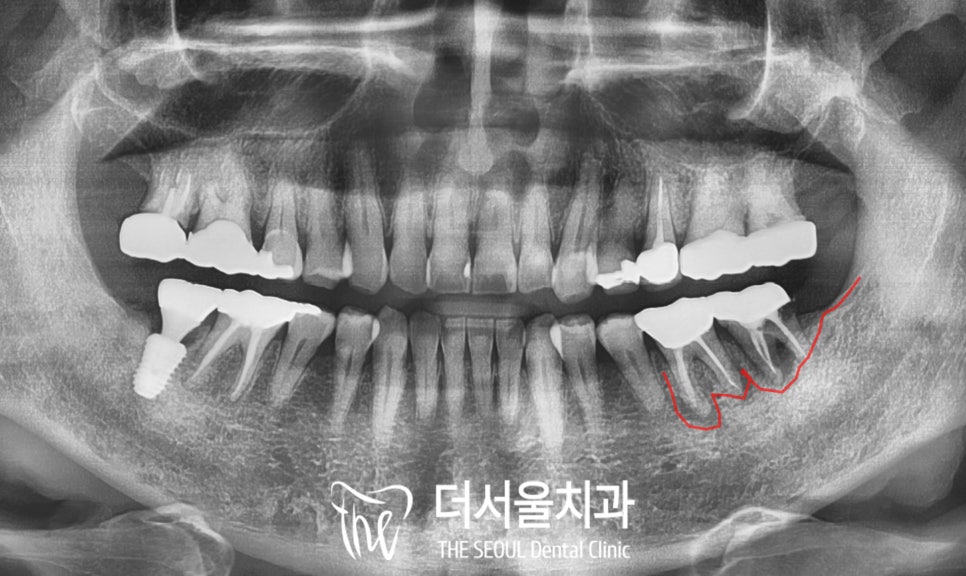

2. 진단 및 계획

수정구 치과 에서

파노라마 엑스레이를 찍어보니

보철로 덮여있어 알 수 없었던

치아 뿌리의 정확한 상태를

파악할 수 있었습니다.

심한 치조골 소실이 있어

치근 끝까지 잇몸뼈가 녹았으며

구치부 두 개의 크라운을 이어둔

브릿지 사이로도

식편압입 및 치태가 많이 쌓여

구취도 있으셨습니다.

치근단 사진을 통해

더 자세히 살펴보면

이전에 신경치료를 하고

크라운을 씌워두었는데

저작력을 끊임없이 받으면서

크라운 안으로 이차우식이 생기고

치아에 조금씩 파절이 생기면서

주변 치주조직을 모두 녹이고 있었습니다.

그렇기 때문에

boneloss가 나타나면서

잇몸에 까만 방사선 투과성 소견이 보입니다.